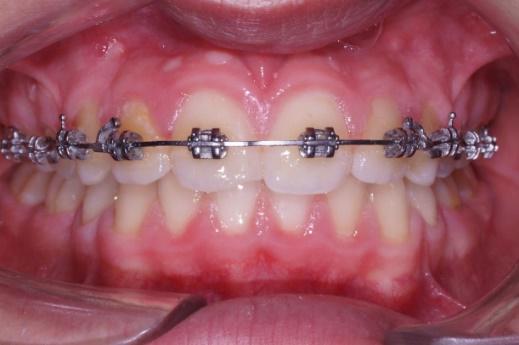

Les progrès en matériau de collage et en métallotechnie permettent de proposer des appareillages plus modernes métalliques et en céramique pour le confort du patient et une pratique plus aisée

Toutes les bagues sont collées y compris les molaires afin de minimiser les risques de caries des bagues qui entourent les dents.